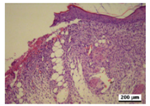

3.5. Histological Analysis